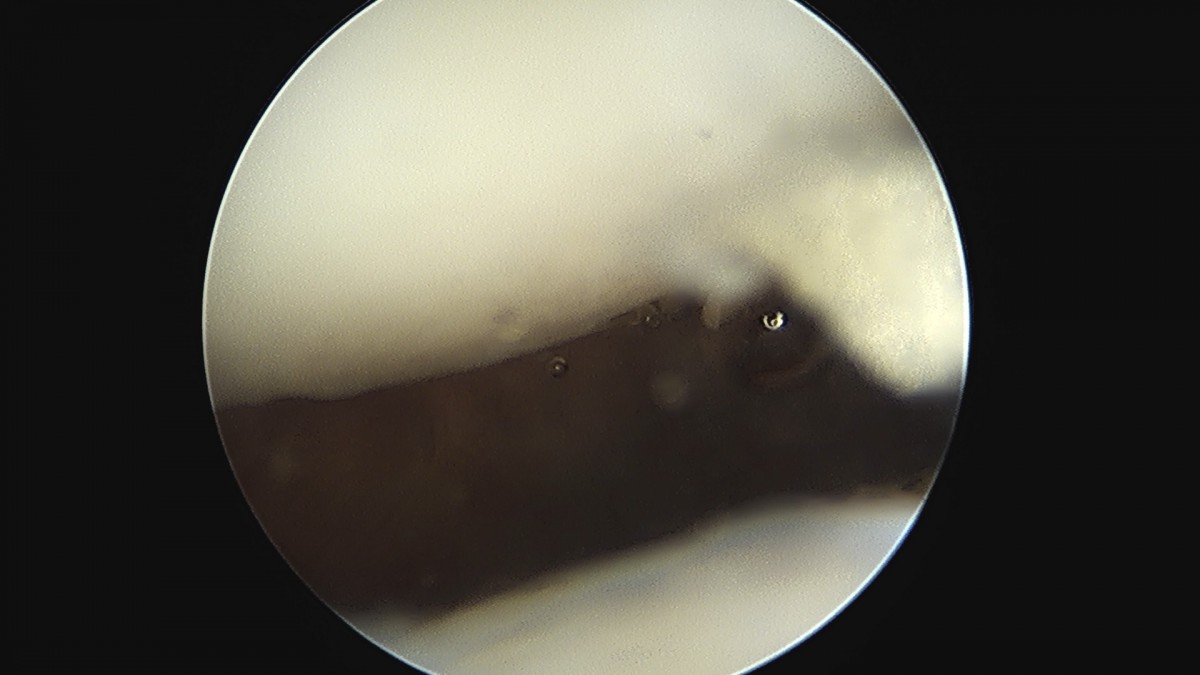

이재상원장님 무릎 반월상 연골판 절제술 안경O 환자

dae765e4d9ac96aee867c9d6292d8784_1758005873_4643.jpg

dae765e4d9ac96aee867c9d6292d8784_1758005874_0351.jpg

dae765e4d9ac96aee867c9d6292d8784_1758005874_6237.jpg

dae765e4d9ac96aee867c9d6292d8784_1758005875_2013.jpg

dae765e4d9ac96aee867c9d6292d8784_1758005875_7729.jpg

dae765e4d9ac96aee867c9d6292d8784_1758005876_3555.jpg

dae765e4d9ac96aee867c9d6292d8784_1758005876_9327.jpg

dae765e4d9ac96aee867c9d6292d8784_1758005877_5099.jpg

dae765e4d9ac96aee867c9d6292d8784_1758005878_0984.jpg

dae765e4d9ac96aee867c9d6292d8784_1758005878_6877.jpg